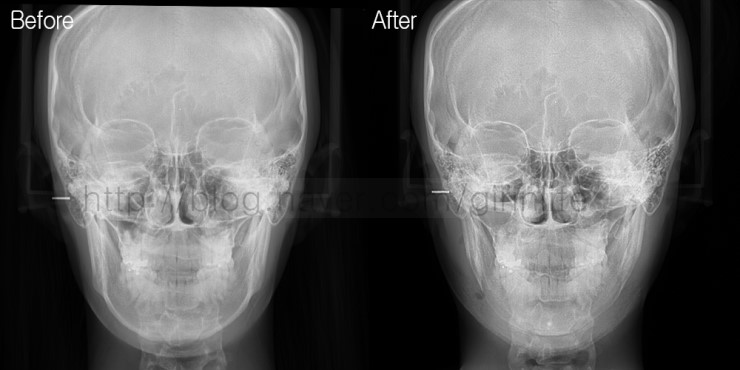

CT를 처음 접하는 사람은 언듯 봐서 차이를 잘 모릅니다. 일일이 수술부위를 짚어가며 설명해드리면 이해를 하시는데 한두번 봐서는 이해가 쉽지 않습니다.

이처럼 윤곽수술을 앞두고 있다면 CT보는 방법을 미리 알아두는 것도 도움될걸로 생각됩니다.

수술전후를 비교할때 정면을 똑바로 향하고 있는지 고개를 들고 있거나 낮추고 있지는 않은지도 체크해봐야 하는데

얼굴뼈CT는 거울을 볼때 고개를 들면 턱이 넓어보이고 고개를 낮춰 올려다보면 갸름해보이는 것과 똑같기 때문에

정확한 판단을 위해서 정중앙, 정면을 바라보고 있는지 확인하시기바랍니다.

수술전 엑스레이를 보면 아래턱라인을 따라 흰색 선이 보여지는데 수술후 엑스레이에서는 보이지 않습니다. 귀밑각부터 앞턱끝까지 절골했다면

이 선이 보이지 않고 귀밑각만 절골했다면 옆턱과 앞턱의 흰색 선이 유지됩니다.